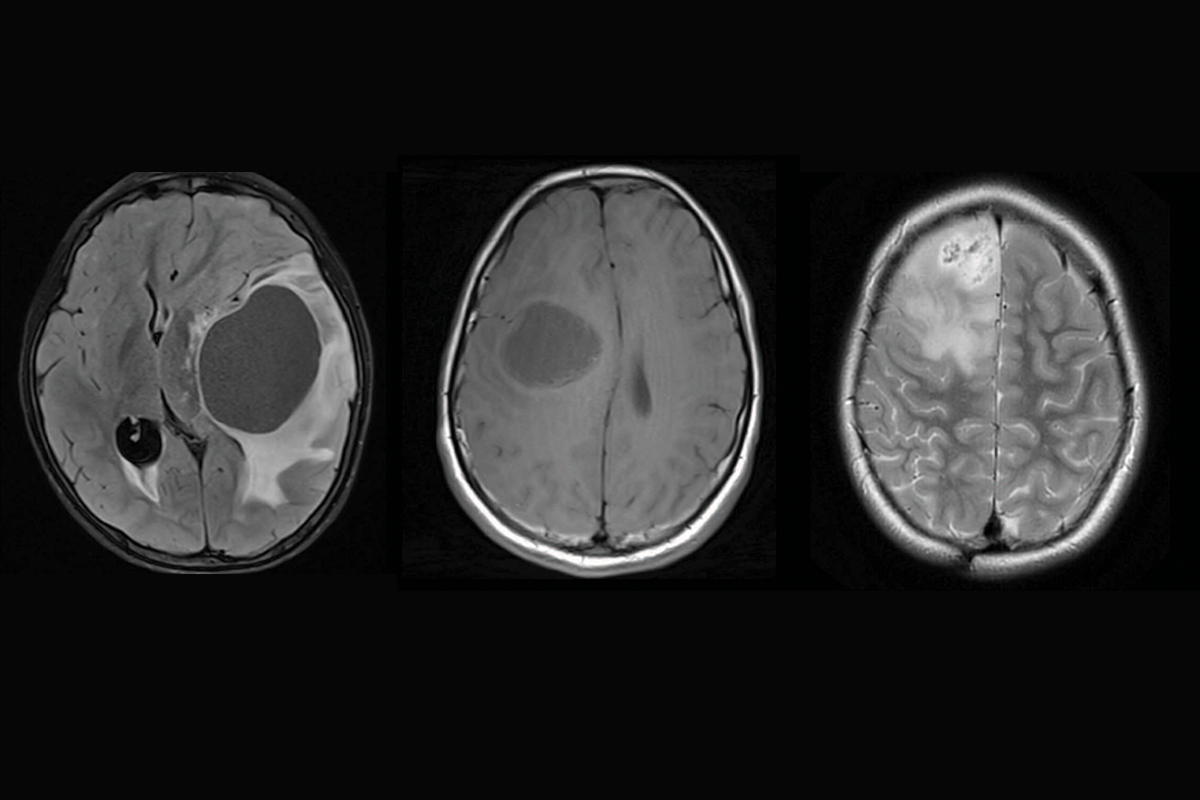

Brain scans showing three different subtypes of priMMRD high-grade glioma.

Discovery of unique brain tumour subtypes offers hope for targeted glioma therapies

SickKids researchers identify three subtypes of high-grade gliomas with distinct treatment responses to provide precision care for patients.